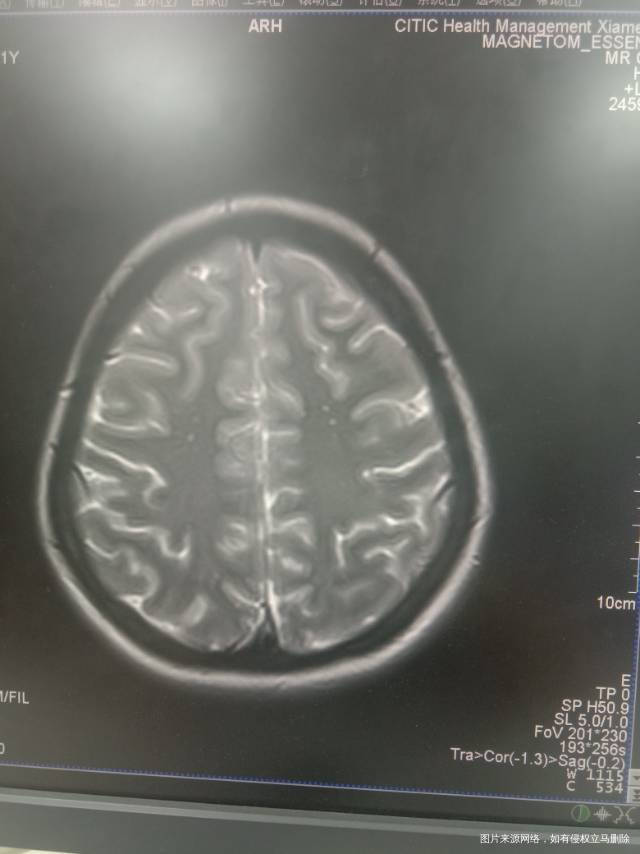

月经初潮开始就不是每个月都很规律,然后去年查了激素才知道是瘦多囊,然后单独吃了几个月哒英,今年六月份到九月份月经都没有来,反而是会分泌褐色分泌物。这几个月还掉发严重,痤疮。上个月又查了激素,餐后血糖,胰岛素释放实验,都超正常值。然后医生就让我吃达英跟二甲双胍,然后我自己还吃NAC,Vd3,混合肌醇。我想问下我这样的话差不多多久去复查?日后能不能手性肌醇代替二甲双胍?最近还做了个头颅磁共振,发现基底节双侧对称钙化 这是因为内分泌引起的吗?还需要做什么检查吗?